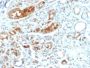

Mammaglobin is a 93 amino acid glycoprotein with homology to other secretoglobin-uteroglobin family members. It was originally identified as a breast cancer restricted biomarker by differential screening. Mammaglobin related to secretoglobin family that includes human uteroglobin and lipophilin. Mammaglobin antibody stains cytoplasm of normal breast epithelial cells as well as primary and metastatic breast carcinomas. Mammaglobin expression is absent in prostate, kidney, colon, rectum, small intestine, stomach, pancreas, lung, and thyroid tissues. Mammaglobin may be used as part of an immunohistochemical panel for determination of metastatic breast carcinoma and tumor of unknown primary origin.Primary antibodies are available purified, or with a selection of fluorescent CF® Dyes and other labels. CF® Dyes offer exceptional brightness and photostability. Note: Conjugates of blue fluorescent dyes like CF®405S and CF®405M are not recommended for detecting low abundance targets, because blue dyes have lower fluorescence and can give higher non-specific background than other dye colors.

Positive Control

SK-BR-3 cells or Breast Carcinoma

IHC, FFPE (verified), WB (verified)

IHC (FFPE) (verified)|WB (verified)

Higher concentration may be required for direct detection using primary antibody conjugates than for indirect detection with secondary antibody|Immunohistology (formalin): 0.1-0.2 ug/mL for 30 minutes at RT|Staining of formalin-fixed tissues requires boiling tissue sections in 10 mM citrate buffer, pH 6.0, for 10-20 minutes followed by cooling at RT for 20 minutes|Optimal dilution for a specific application should be determined by user